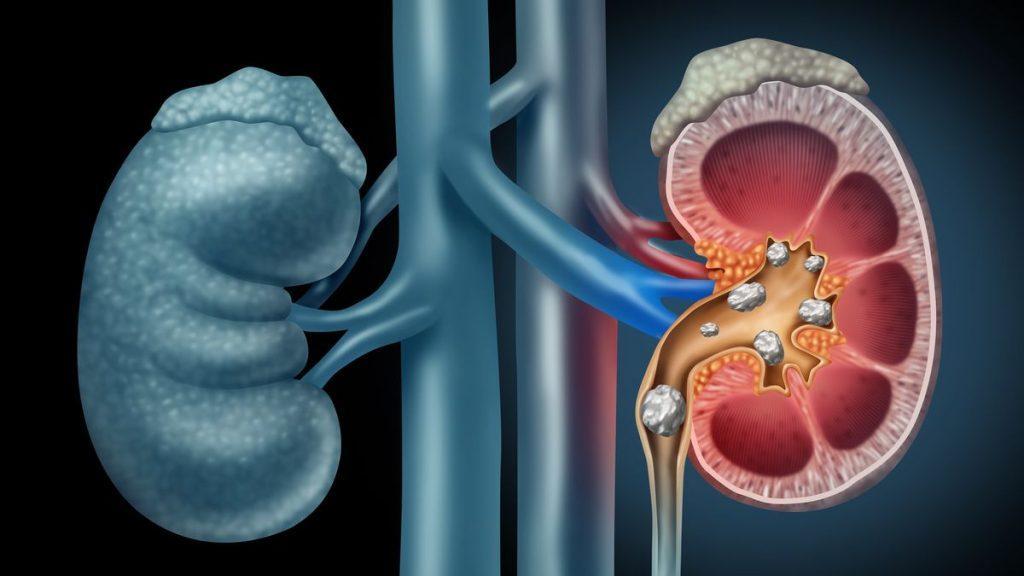

Les calculs rénaux sont une affection courante : on estime que jusqu’à 15 % des personnes en souffrent à un moment donné de leur vie. Si la plupart d’entre eux passent spontanément, certains patients doivent subir une intervention chirurgicale afin d’éviter des dommages permanents aux reins.

Baptisée lithotripsie par salve d’ondes sonores (BWL), la nouvelle approche utilise de courtes rafales harmoniques d’énergie ultrasonore pour briser les calculs rénaux en fragments de 2 millimètres ou moins. Contrairement à la méthode actuelle, elle peut être administrée dans un cadre plus informel, à l’aide d’un appareil portatif et sans sédation.

Son efficacité a été démontrée chez 19 patients subissant une urétéroscopie pour des calculs rénaux. La BWL a été administrée pendant la procédure chirurgicale, ciblant individuellement jusqu’à trois gros calculs (≤12 mm) pendant 10 minutes. Ce qui s’est traduit par la fragmentation de 90 % du volume total des calculs : avec 39 % d’entre eux complètement fragmentés (morceaux de moins de 2 mm) et les 52 % restants l’étant partiellement.